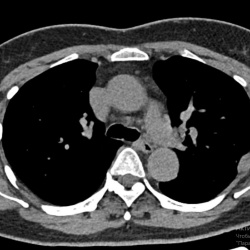

Женщина 70 лет. Архива нет. В левом легочном поле, тень имеющая двойной контур, ГПОД?

Без жалоб на это образование.

Периодически встречаю такое. Нигде не могу найти ответ что за штука такая.

Если кто знает подскажите.